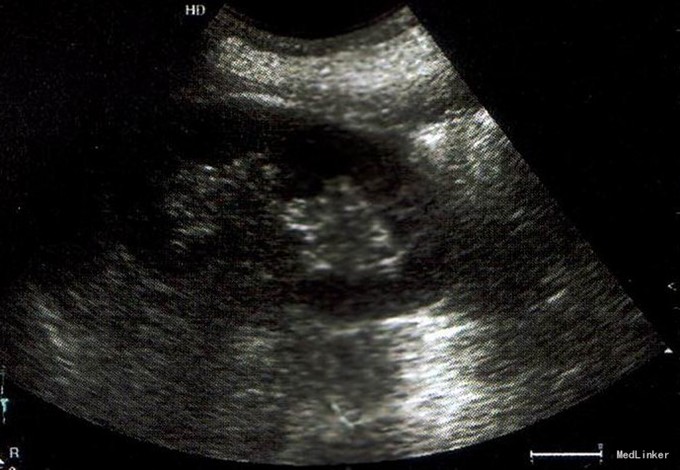

妇检:外阴:发育正常;阴道:通畅,未见异常分泌物,嘱患者用腹压情况下前后壁全部脱出阴道口,粘膜稍充血,水肿;宫颈:宫颈全部脱出阴道外。宫体:萎小,无压痛,仍在阴道内。双附件:未扪及明显包块,无触痛。 泌尿系,肝胆脾胰,妇科,心脏B超报告见下图。